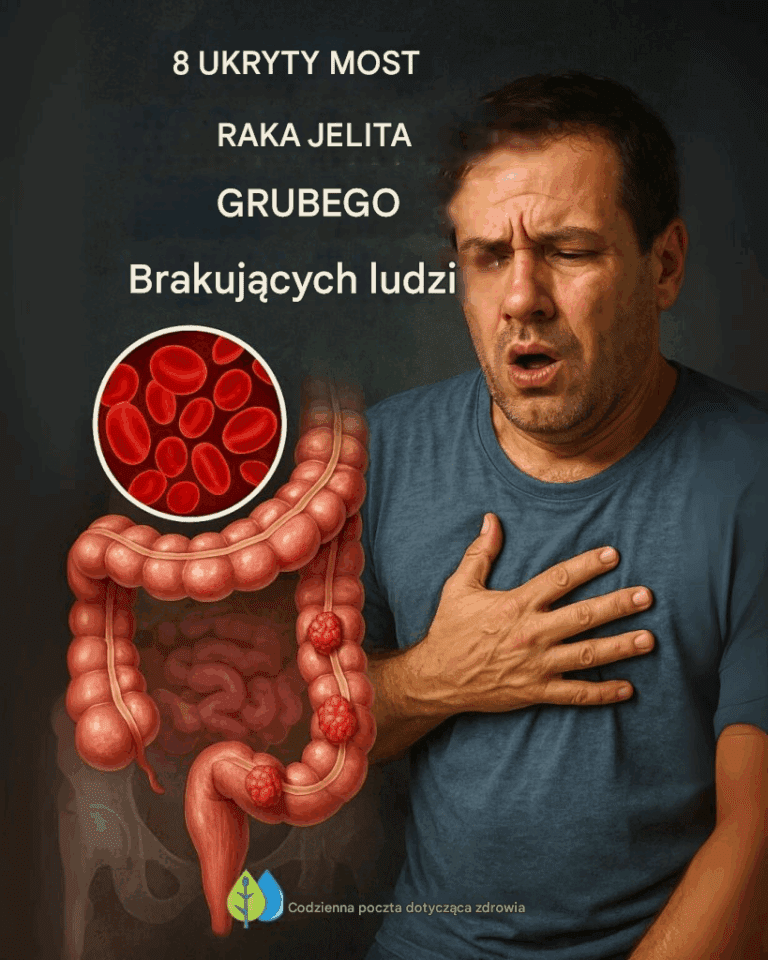

Już wiesz, jak ważna jest zdrowa flora jelitowa, zwłaszcza w obliczu alarmującego wzrostu zachorowań na raka jelita grubego wśród młodych ludzi. Ale jeśli szukasz…

Rak jelita grubego to poważny problem zdrowotny, który staje się coraz powszechniejszy, zwłaszcza wśród osób młodych. Wskaźnik zachorowalności wśród osób poniżej 55. roku życia…